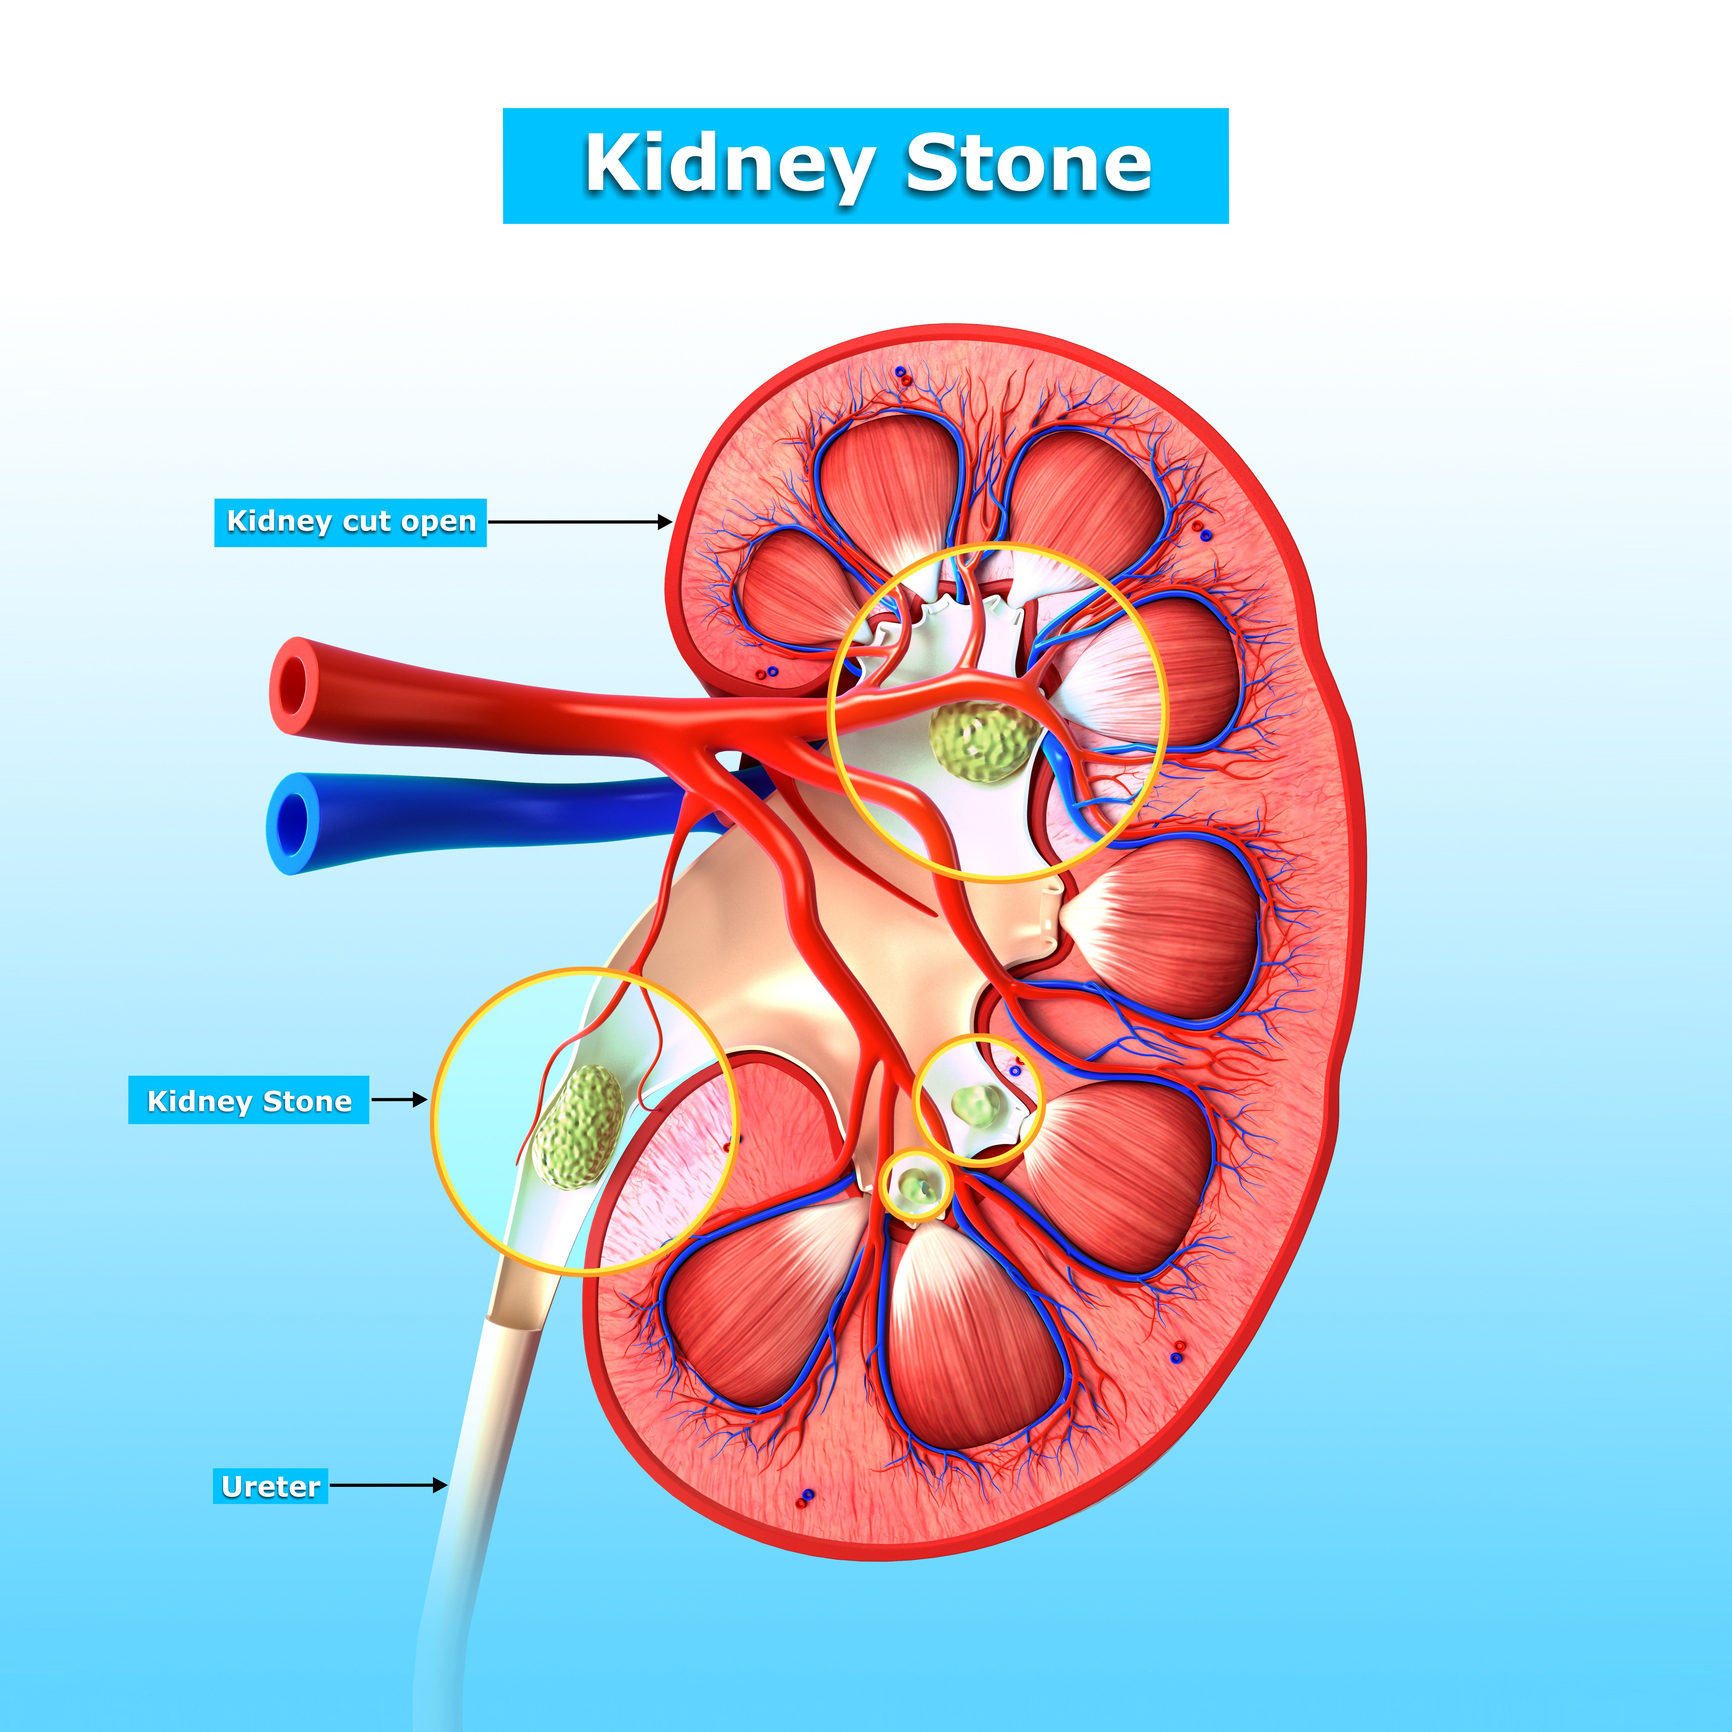

Dehydration can lead to kidney stones, kidney failure, and cardiac arrest

Dehydration can lead to kidney stones, kidney failure, and cardiac arrest. The risk of dehydration is much higher in the summertime, as the weather is hotter and people are outdoors and being active more often. While running low on liquid intake is usually associated with weakness and malaise, you should also know without proper hydration ...click here to read more